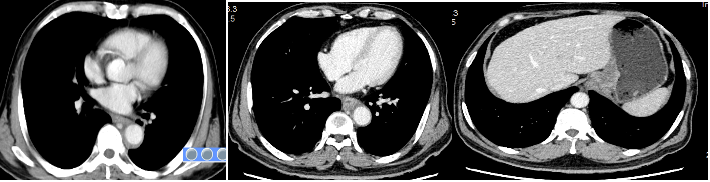

替雷利珠单抗+化疗联合治疗4周期后影像

2周期治疗后患者吞咽困难症状缓解。2、4周期复查CT:胸下段及腹段食管癌并纵隔淋巴结转移累及胃贲门较前明显缩小,胃小弯侧及腹膜后多发淋巴结转移累及胃小弯壁较前明显退缩。后续计划提交本院食管癌MDT讨论拟定下一步行手术或局部放疗。

该患者为晚期食管癌,食管病灶长,并累及贲门及胃小弯,纵膈淋巴结、胃小弯淋巴结及腹膜后淋巴结广泛转移,一线予以替雷利珠单抗联合紫杉醇、奥沙利铂治疗,获得了很好的疗效,肿瘤快速退缩,临床症状迅速得以缓解,疗效评价PR,且治疗耐受性好,没有出现免疫治疗相关不良反应,目前仅胃小弯局部残留,计划近期全面复查,评估肿瘤情况,同时提交我院食管癌MDT讨论下一步局部治疗的可行性,同时继续予以替雷利珠单抗全身维持治疗。